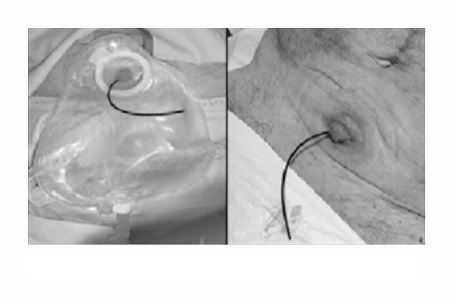

Una ureterostomía cutánea es una derivación heterotópica no continente que se realiza tras una cistectomía. Es una técnica en la que el uréter se aboca a la piel de forma directa, evertiendo el uréter sobre la piel, sin necesidad de usar ninguna parte del segmento intestinal disminuyendo así, el riesgo de complicaciones (figura 1). Uno de los inconvenientes de esta técnica es la necesidad de llevar sondas de ureterostomía para evitar estenosis, lo que conlleva un aumento del riesgo de contraer infecciones ya que existen estudios que datan una prevalencia de ITU en portadores de derivación urinaria definitiva del 42,8% 4,5.

En programa de hemodiálisis desde 2019 y portador de fístula arteriovenosa autóloga radio-cefálica izquierda. En las pruebas pre-trasplante, el equipo de urología le explica que el trasplante renal conlleva la realización de una ureterostomía cutánea permanente. El paciente acepta y entra en lista de trasplante en enero del 2023. En febrero se realiza dicho trasplante renal y la ureterostomía cutánea paramedial izquierda con catéter simple J (Figura 1).